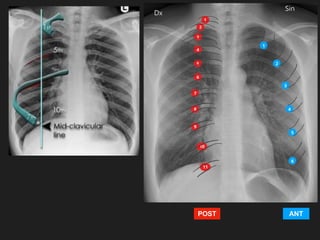

Criterios de ‘calidad’

R.I.P.

• Rotación: Los procesos espinosos se

encuentran en un punto medial entre

las clavículas.

• Inspiración: Al menos 5 a 7 costillas

anteriores o 8 a 9 costillas posteriores

por arriba del diafragma en la línea

medio clavicular. Escápulas fuera del

tórax

• Penetración: Columna debe ser visible

detrás del corazón, vasos en ápices

pulmonares y a través del corazón.

Criterios de ‘calidad’: INSPIRACIÓN/ESPIRACIÓN

INSPIRACIÓN ESPIRACIÓN

Elevación

diafragmática

Agrupación

vascular, falsa

congestión

ANT

POST

Radiografías en espiración:

Detectar pequeños neumotórax.